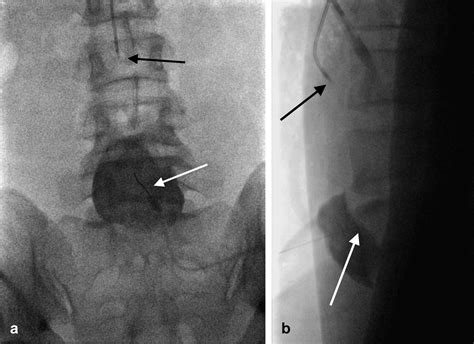

The procedure is typically performed under fluoroscopic or CT guidance to ensure accurate placement of the needle. The patient is usually positioned prone, and the needle is inserted through the skin and advanced to the target area. Once the needle is in place, the anesthetic and/or corticosteroid is injected.

• Computed Tomography (CT): CT scans provide detailed images of the pelvic region and can help identify the location of the Superior Hypogastric Plexus and any associated pathologies.

• Fluoroscopy: Fluoroscopy is often used during interventional procedures to guide the placement of needles or catheters into the Superior Hypogastric Plexus.

Interventional procedures, such as nerve blocks or neurolysis, can provide targeted relief from chronic pelvic pain. These procedures are often performed under imaging guidance to ensure accurate placement of the needle or catheter.